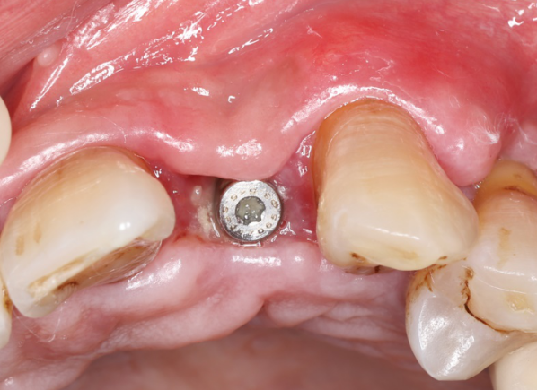

旋入种植体,初期稳定性为 30N。

直接上愈合基台。

术后8周

牙龈软组织愈合,角化附着龈健康,口腔卫生一般,嘱患者重视日常口腔卫生维护。

术后4.5个月口内照片

术后4.5个月根尖片

ISQ动度值颊舌/近远中为70/73。